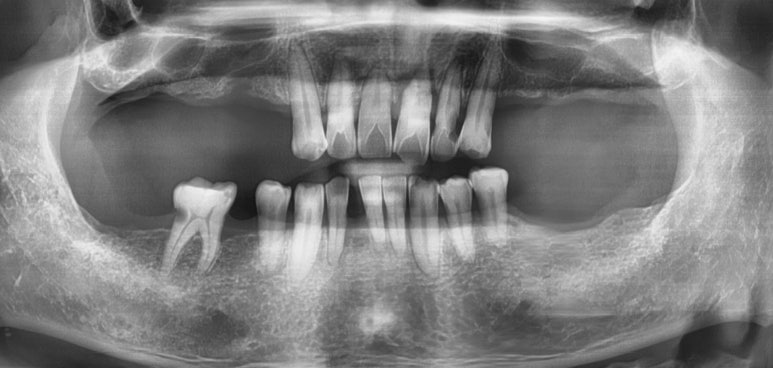

많이 흔들리는 치아들은 엑스레이 상에서 치아뼈가 많이 녹아있어 치아뿌리를 거의 잡아주지 못하고 있었구요

![[치과브릿지케이스] 앞니가 너무 많이 흔들려서 발치해야 할 것 같아요 관련 이미지 3](https://pub-9f2bb3498faf4d1d8714b41df24753e3.r2.dev/content/clinics/archive/rseeanjxfu/naver_blog/yonseiyegam/assets/by_hash/516c26ca6135a778aa3e835e80554e8dd4660927dcaad2a394eae7f3a67bfe00.jpg)

치아를 부딪히는 사고도 당하셨다고 합니다.

자세히 보는 정밀 엑스레이를 찍어봤더니

치아 뿌리가 가로로 부서진 것을 볼 수 있었습니다.

당연히 흔들릴 수 밖에 없겠죠.

임플란트와 브릿지 중 환자분과 상담하여 브릿지를 하기로 하였구요